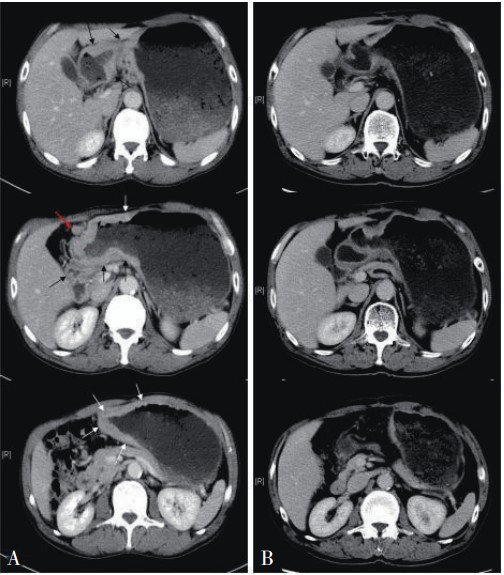

中年男性,肺癌,肝转移,多程化疗后

胸膜转移(附黄勇老师谈肺癌肝转移)